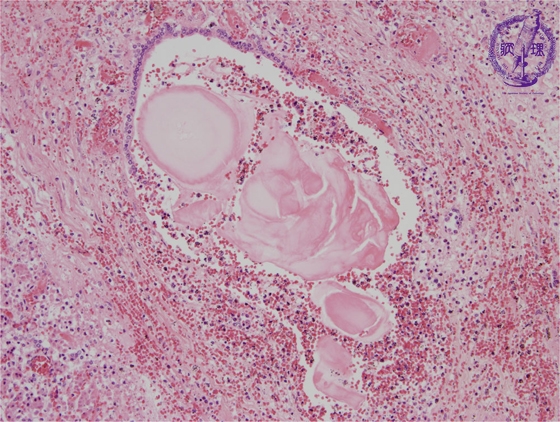

Microscopic image(HE stain, mid-power): There is destruction of the pancreatic duct epithelium and residual pancreatic ducts contain concentrated proteinaceous material. The inflammatory cell infiltrate is composed mainly of neutrophils.